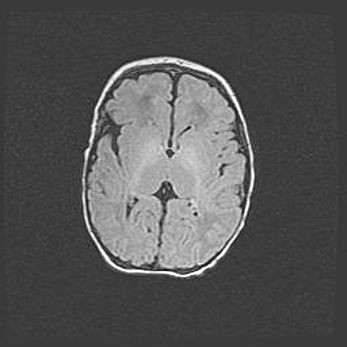

Лейкомаляция с кистозно-глиозной дегенерацией головного мозга.

Возраст: 2 месяца 25 дней

Вес: 6400 г

Окружность головы: 40 см

Срок гестации: 41 неделя

Лейкомаляцию относят к ишемически-гипоксическим повреждениям головного мозга, диагностируемым у новорожденных. При лейкомаляции в головном мозге обнаруживают очаги некроза, возникшие после тяжелой гипоксии и нарушения кровотока. В процессе морфогенеза очаги проходят три стадии: 1) развития некроза, 2) резорбции и 3) формирования глиозного рубца или кисты. Перивентрикулярная лейкомаляция (ПЛ) встречается примерно в 12% случаев среди новорожденных, обычно – у недоношенных детей, причем, частота ее зависит от массы, с которой младенец появился на свет. Наибольшее число малышей страдает лейкомаляцией, если масса при рождении 1500-2500 г.